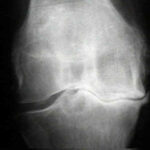

A worker sprained her knee when sitting down on an employer’s bus. An MRI found that she’d torn her medial meniscus. But her workers’ comp claim for the injury was denied because sitting down was a ‘normal body movement’ and the injury wasn’t related to a workplace hazard. On appeal, the Appeals Commission ruled that the worker’s injury was compensable. When the worker boarded the employer’s bus, which she was required to take, she was wearing PPE and a heavy backpack. The bus was crowded, and the aisle and seats were narrow. The worker had to twist and turn to remove her backpack and get into her seat. While doing so, she heard her knee ‘pop.’ The Commission found that the ergonomic conditions on the bus, which included the limited turning radius in the aisle and the limited size of the bus seat, were employment hazards that led to the worker’s need to turn and or twist to sit down into her seat and caused her knee injury [2016-0776 (Re), [2016] CanLII 87362 (AB WCAC), Dec. 15, 2016].